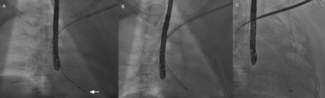

A 62-year-old woman with atrial fibrillation was admitted to Sichuan Provincial People’s Hospital, and radiofrequency ablation therapy was planned. After femoral venous puncture, X-ray fluoroscopy showed a slim-line shaped wire that was...